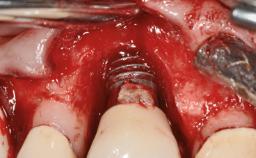

The fracture of an implant after it has been restored is one of the most severe complications. It most frequently occurs in partially edentulous jaws (1.5%). Most implant fractures involve implants with a diameter of 3.75 mm made of commercially pure titanium (Eckert 2010). Unfortunately, many cases are not reported or documented by the clinicians involved in resolving the problems created by the fracture. This case report describes the management of an implant fracture at site 36 in a middle-aged male patient. The implant had been restored with a screw-retained metal-ceramic crown.